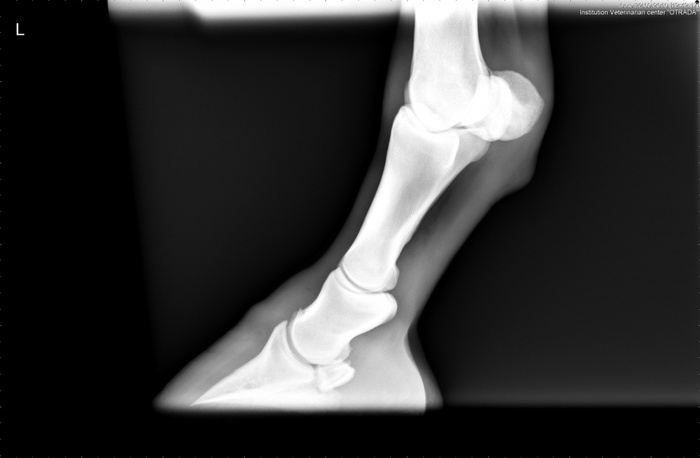

Рентгены ноги

перелом

Сейчас

Здоровая нога для сравнения

Одна из причин такого продолжительного времени срастания кости скорей всего кроется в проседании кости после снятия штифтов. Изначально, при переломе, кость очень сильно просела. На штифтах вытянулась, стали нарастать ткани. Когда штифты сняли ткани не выдержали и кость снова просела. (Их сняли раньше назначенного срока из-за подозрений на проблему с костью). Соответственно все ткани, образовавшиеся за это время, порвались. И с того момента, как кость приняла «окончательную позицию», весь процесс можно сказать пошёл заново...